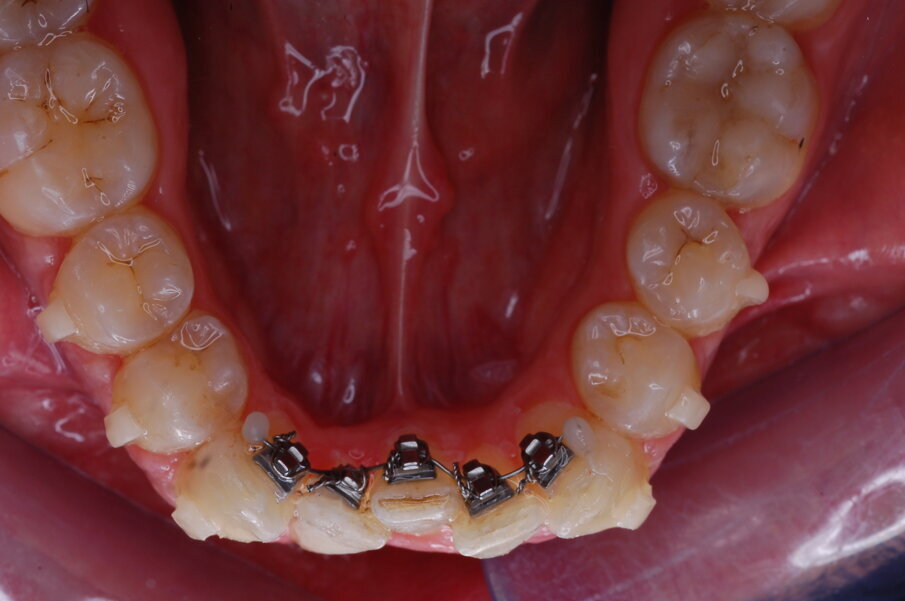

Diagnosi ed eziologia Un uomo sano di 39 anni si è presentato nel nostro studio ortodontico lamentando un aspetto dentale poco attraente e la paura della chirurgia ortognatica proposta da un altro ortodontista. Clinicamente, il profilo del paziente era rettilineo e la vista frontale non mostrava alcuna asimmetria facciale. L’esame funzionale non ha rivelato alcuna deviazione mandibolare o riduzione dei movimenti. Il paziente non aveva dolori articolari e non sono stati rilevati rumori articolari. Era presente una lieve occlusione molare bilaterale di Classe II, un morso aperto e un grave affollamento in entrambe le arcate. L’affollamento era particolarmente grave nell’arcata mandibolare, sebbene mancasse l’incisivo centrale mandibolare destro. Gli incisivi mascellari erano di piccole dimensioni, suggerendo una discrepanza dell’indice di Bolton se fossero stati presenti tutti e quattro gli incisivi mandibolari. Erano inoltre presenti un morso incrociato nella regione dell’incisivo laterale superiore sinistro e una grave rotazione distale del secondo premolare mandibolare sinistro (Figg. 1-8).

Figg. 1-8_Fotografie facciali e intraorali pre-trattamento.